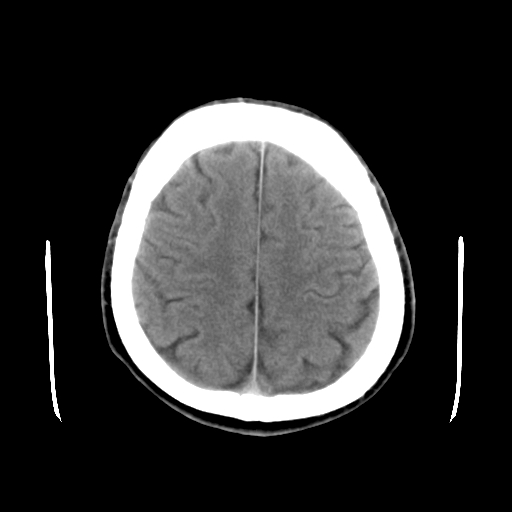

标题: CT15194:男,53岁,头痛、恶心三天。 [打印本页]

男,53岁,头痛、恶心三天。

筛窦囊肿、颅内未见明确异常